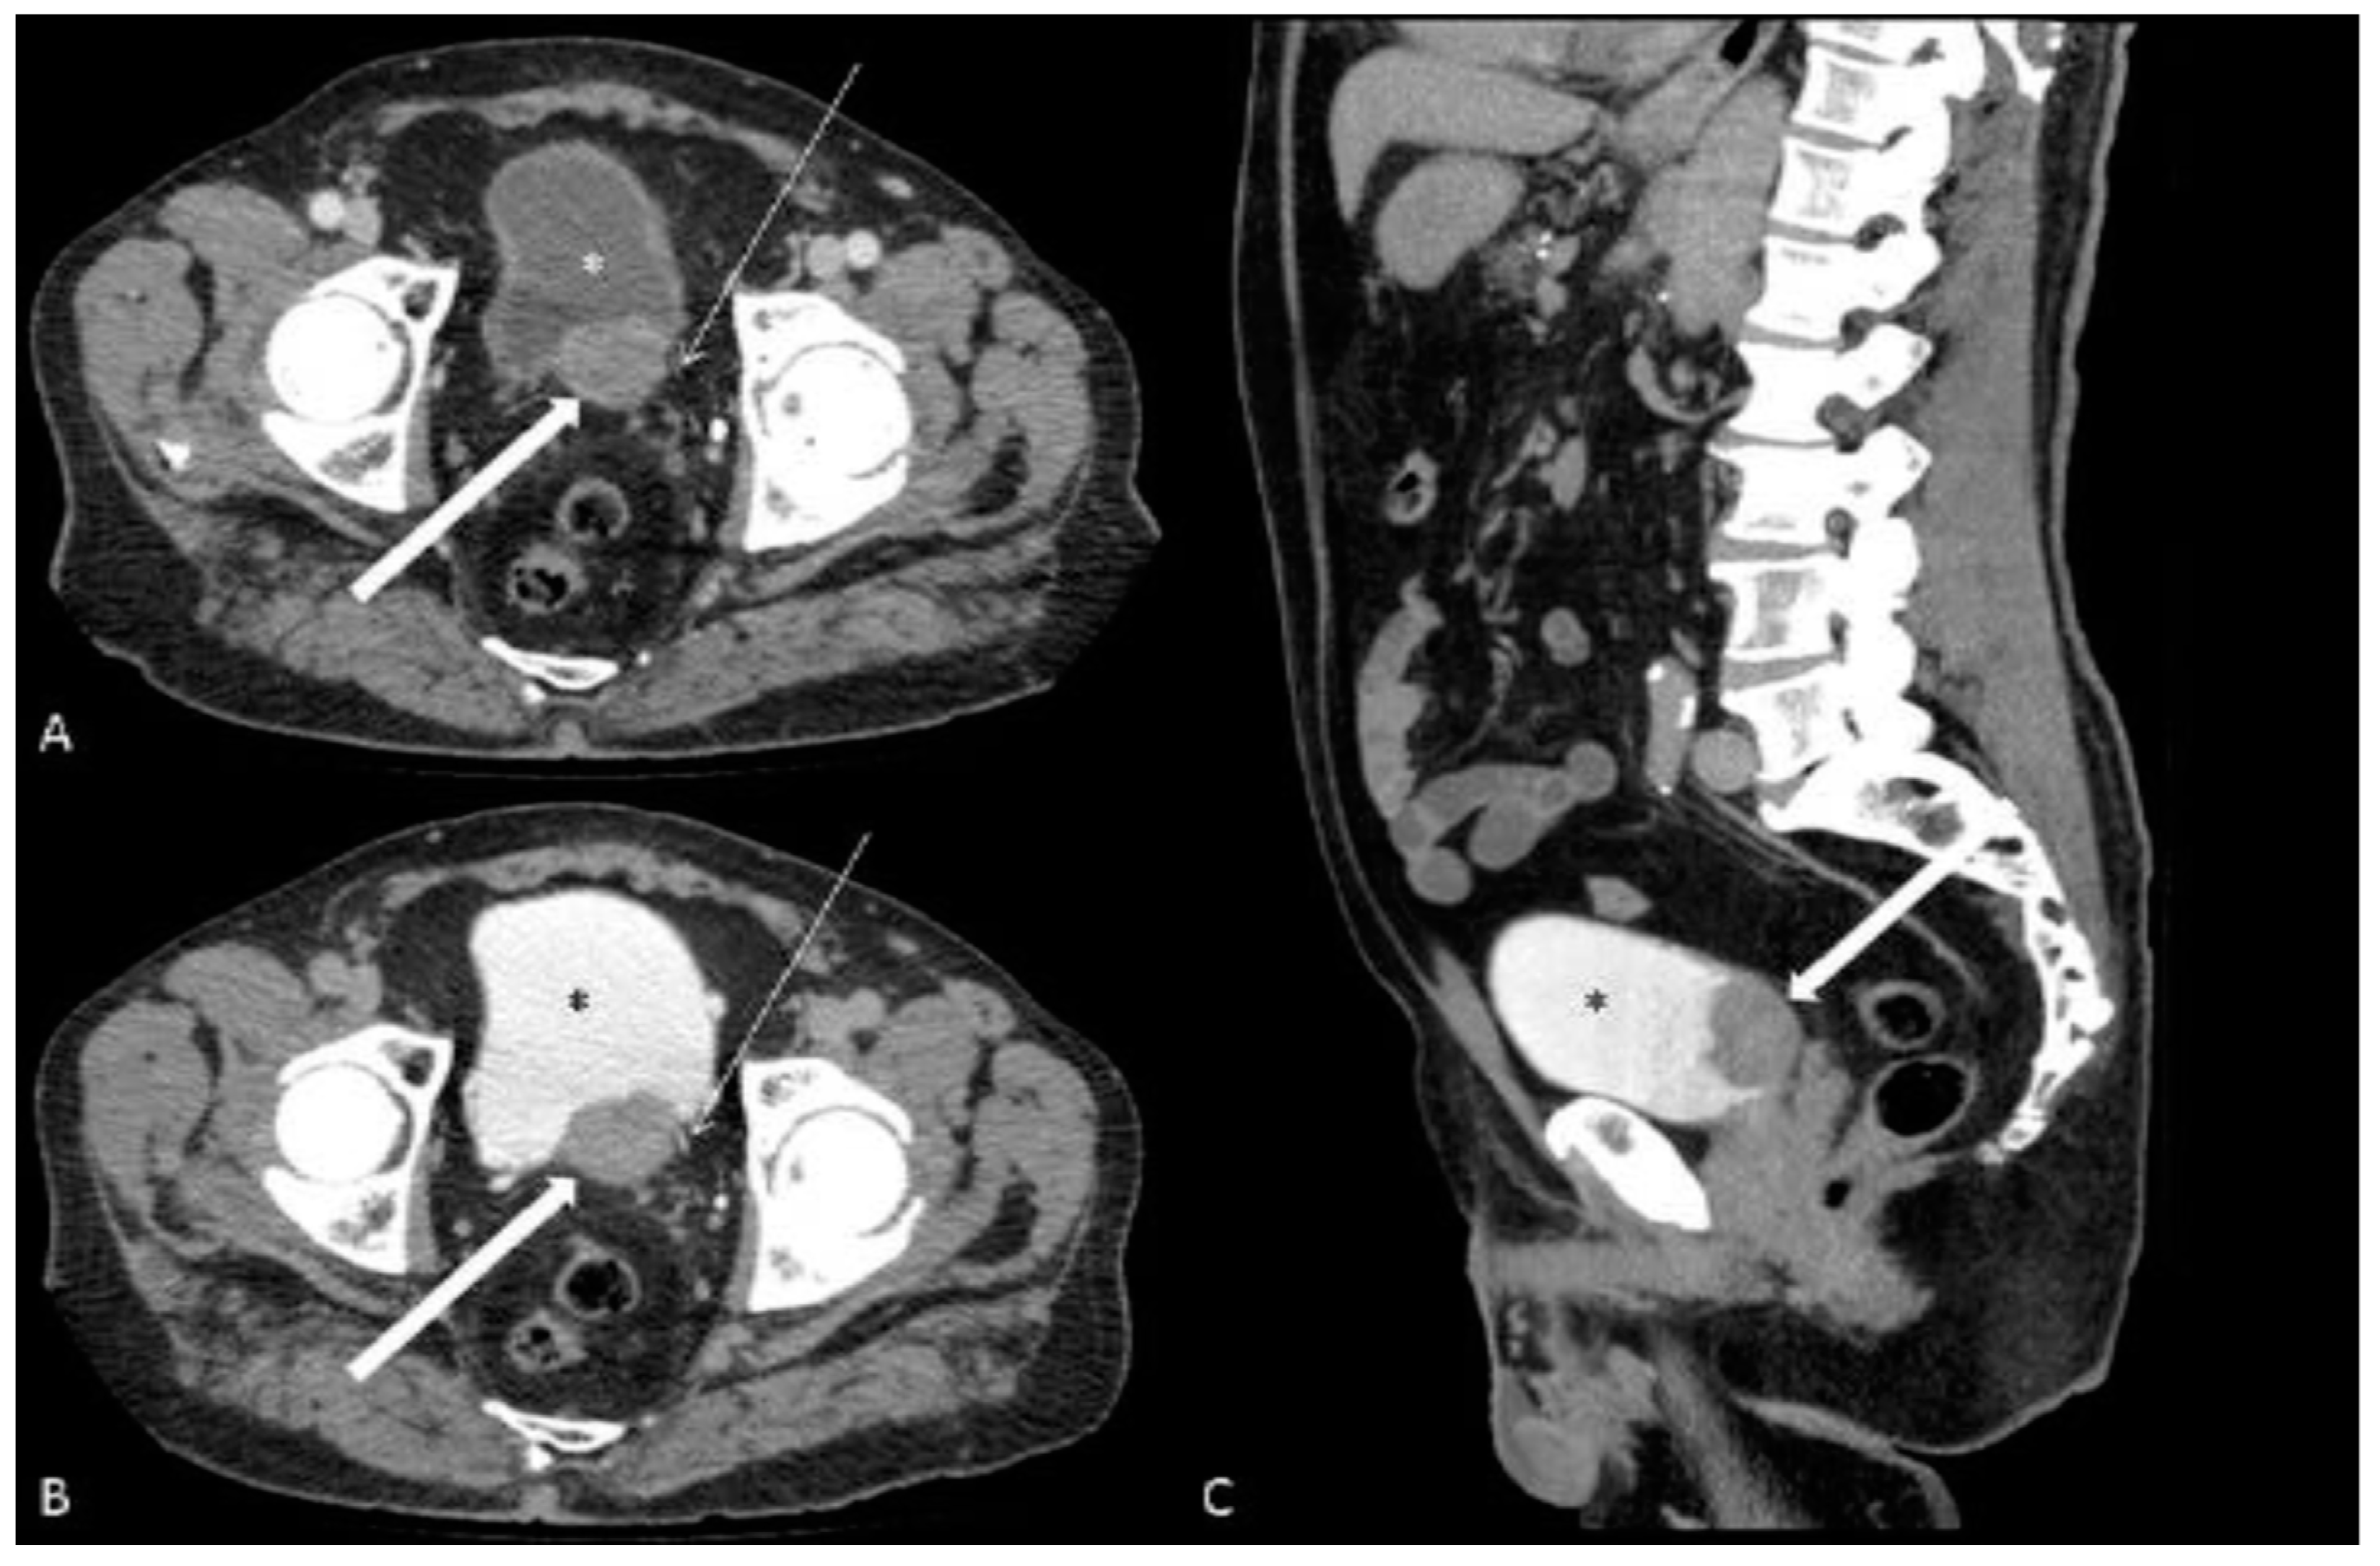

| Present study | # 1 | M | 79 | yes | no | yes | yes | PT | 3.1 × 2.3 | 67 | ill | no | no | 11 | 6,5 | yes | yes | no | Liver |

| # 2 | M | 83 | yes | no | yes | yes | ALT | 9.5 × 4.5 | 30 | sharp | no | no | 17 | 32 | yes | no | no | no | |

| # 3 | M | 76 | yes | yes | yes | yes | ART | 6.0 × 3.2 | 51 | sharp | no | no | 6 | 25 | yes | no | no | Liver | |

| # 4 | M | 56 | yes | yes | yes | yes | PRT | 8.4 × 7.8 | 38 | ill | no | no | 19 | 21 | yes | yes | yes | Bone | |

| # 5 | M | 62 | yes | no | yes | no | ALRT | 15.1 × 12.6 | 55 | ill | no | yes | 43 | 17 | yes | yes | yes | no | |

| # 6 | M | 75 | no | yes | yes | no | T | 3.3 × 1.6 | 44 | ill | no | no | 14 | 5 | no | no | no | no | |

| # 7 | M | 84 | yes | no | yes | no | PLART | 12.4 × 12.2 | 31 | sharp | no | no | 30 | 9,5 | yes | yes | yes | no | |

| # 8 | M | 70 | yes | yes | yes | no | PT | 3.6 × 1.7 | 34 | sharp | no | no | 9 | 10 | yes | yes | no | no | |

| # 9 | M | 85 | yes | no | no | yes | A | 4.5 × 2.0 | 84 | ill | no | no | 17 | 5 | yes | no | no | no | |

| # 10 | M | 76 | yes | no | yes | yes | PRT | 3.0 × 3.3 | 59 | ill | yes | no | 15 | 5 | no | no | yes | no | |

| # 11 | M | 83 | yes | no | no | yes | PT | 5.0 × 2.5 | 57 | ill | no | no | 17 | 13 | yes | no | no | no | |

| # 12 | M | 76 | yes | no | yes | no | T | 2.5 × 1.9 | 49 | ill | no | no | 10 | 8 | no | no | no | no | |

| # 13 | M | 83 | yes | yes | no | yes | PR | 3.0 × 1.3 | 68 | ill | no | no | 15 | 5 | yes | no | no | no | |

| # 14 | M | 83 | yes | no | no | yes | PL | 2.5 × 2.5 | 48 | ill | yes | no | 2 | 22 | yes | no | yes | Liver | |